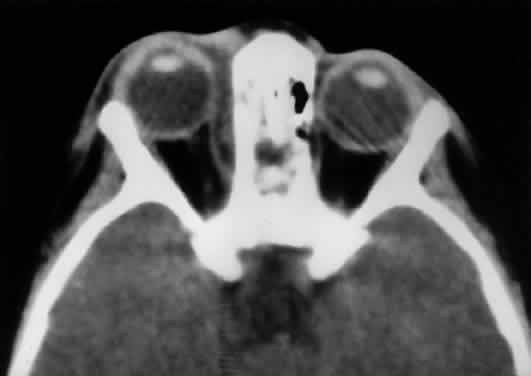

Fig. 17. The optic nerve (ON). A parasagittal MR image demonstrates the 7-mm excess of intraorbital optic nerve, seen as an S shape. Also note the perpendicular relation of the inferior oblique muscle (IOM) to the inferior rectus muscle (IRM). Other findings of anatomic interest in this image include the levator (Lev), the superior rectus muscle (SRM), the orbital septum (OS) arising from the arcus marginalis, and the preaponeurotic fat pad (PF) between the septum and the levator. Note that the orbital floor (FL) is angled upward by 15° to 20° from anterior to posterior.